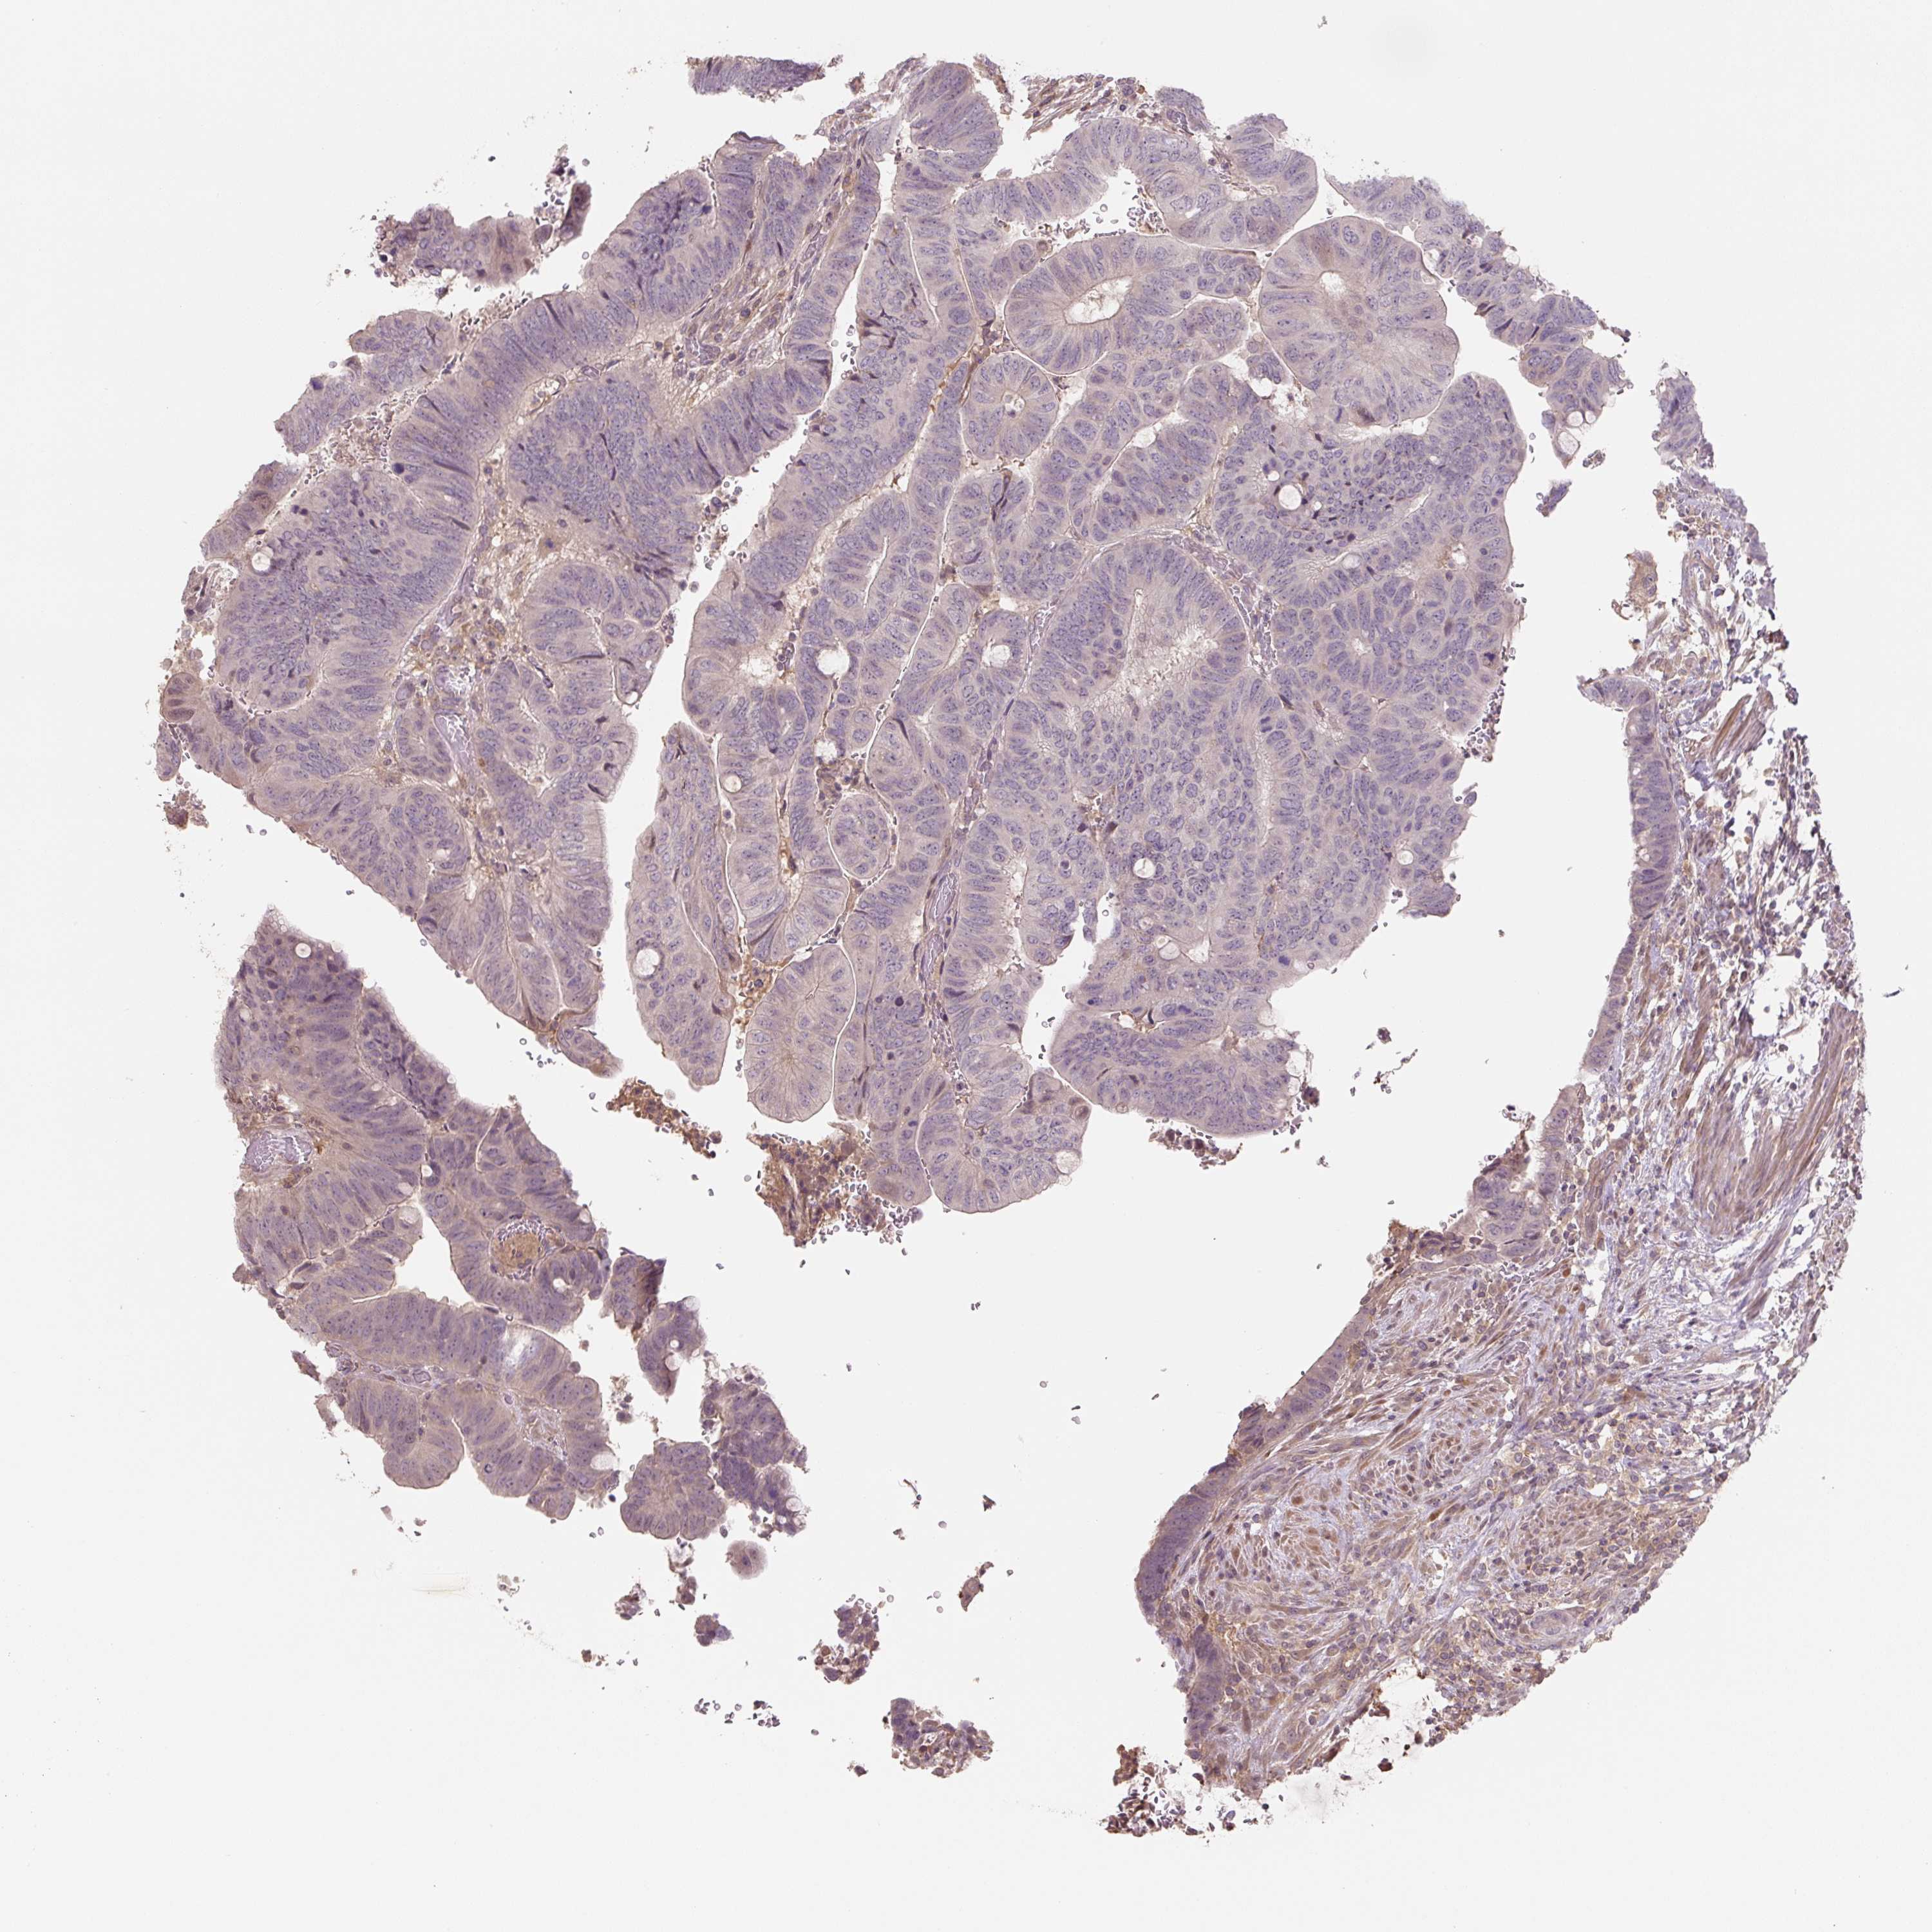

Colorectal cancer

Human cancer

Colon adenocarcinoma

Rectum adenocarcinoma